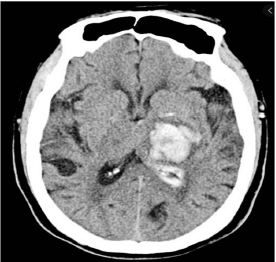

À admissão, está com FC 66, PA 198x118 e glicemia capilar de 275mg/dL. Realizada TC de crânio, exibida abaixo.

Assinale a opção que indica a única medida que não melhora o desfecho neurológico deste doente.